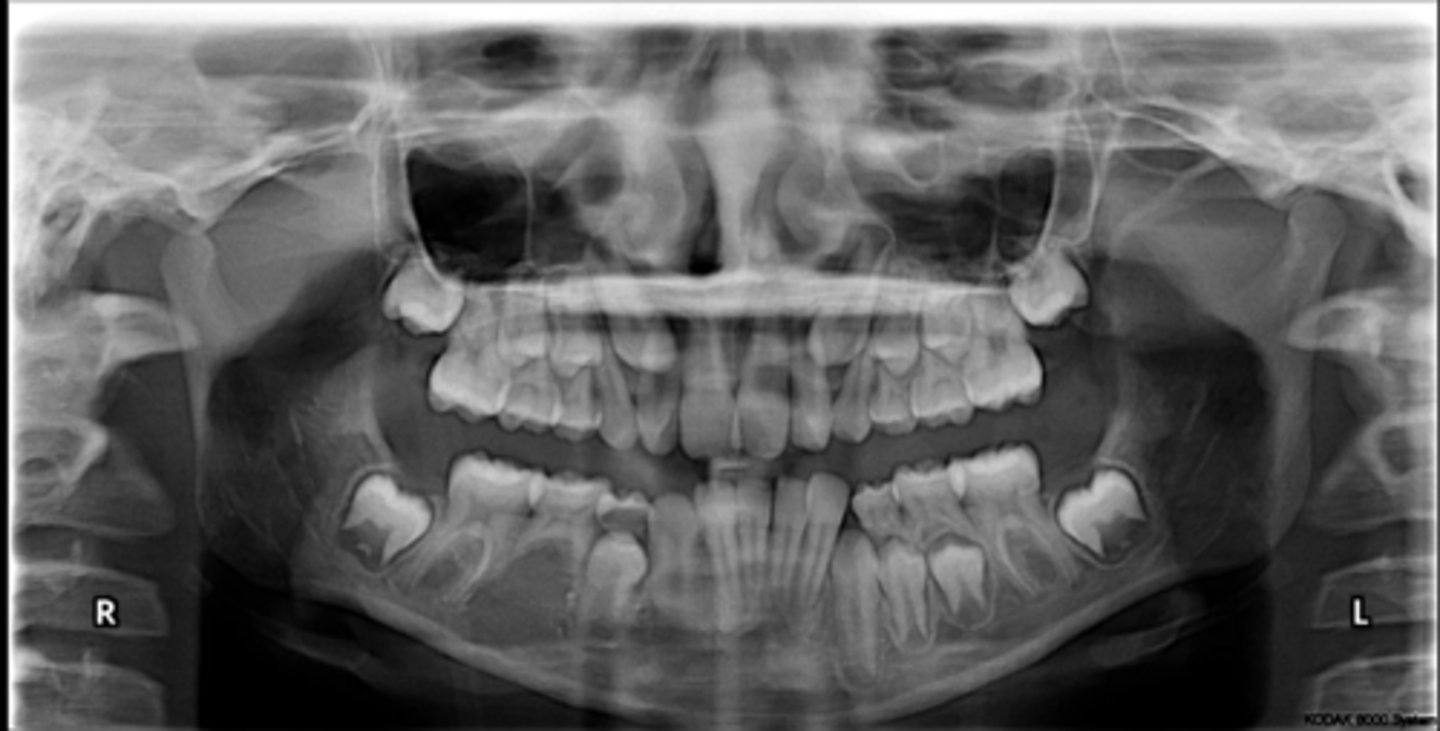

Class II skeletal (very light)

What type of skeletal malocclusion is this patient?

Hypodivergent

Are the hyper-, hypo-, o normo- divergent?

proclined

Maxillary incisors are?

Class II

Hyperdivergent

Class I

Normodivergent

No

Are the maxillary incisors proclined/flared?